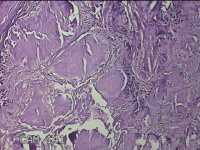

左外踝包块

性别

男

年龄

31岁

临床诊断

皮下结节

一般病史

发现左外踝包块1年余。

标本名称

大体所见

灰白暗红色包块1.8x1.3x0.7cm一个,表面糜烂,切开包块,内见大量石灰样物,内壁粗糙。

去了解病史,应该是痛风结节。